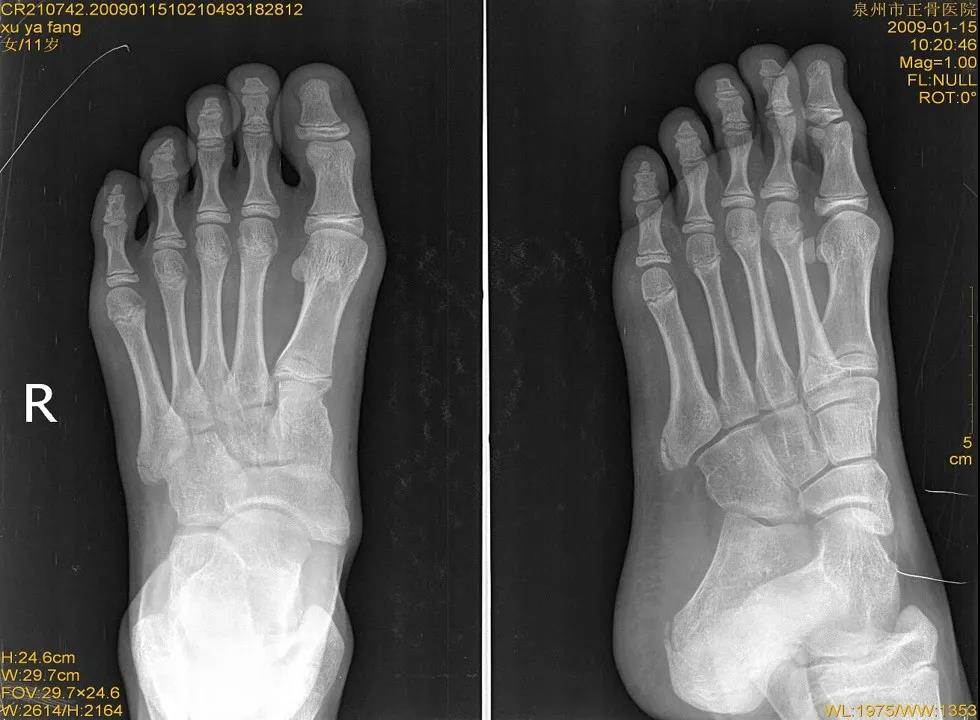

X线

儿童骨骺未闭

腓骨下骨

距后三角副骨

籽骨

儿童正常骨骺